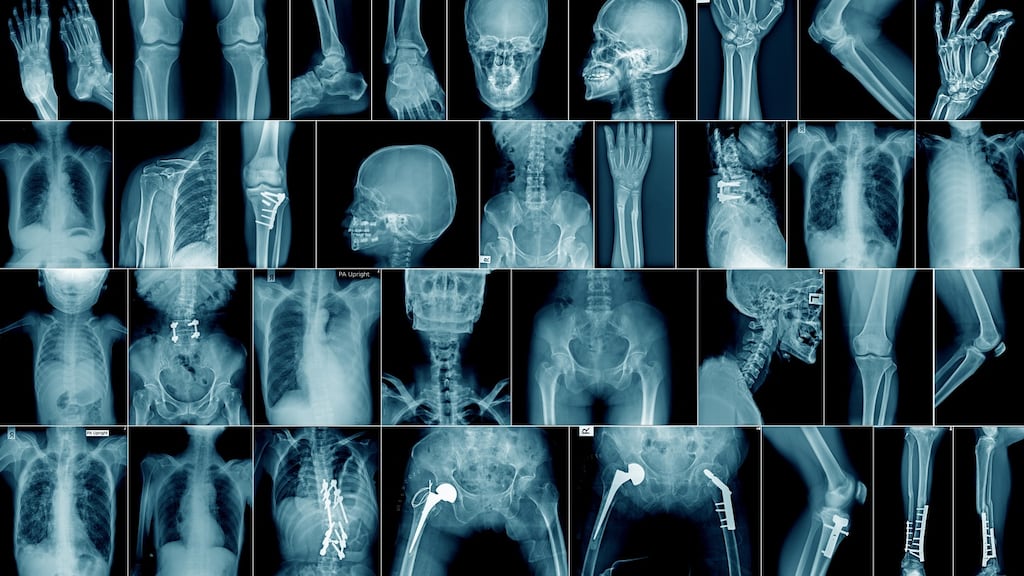

X-rays are a routine diagnostic aid . . . but are they overused?

X-rays, Ryan adds, are used safely every day worldwide, allowing radiologists to diagnose diverse conditions by generating conventional radiographs and/or three-dimensional computed tomography (CT) images.